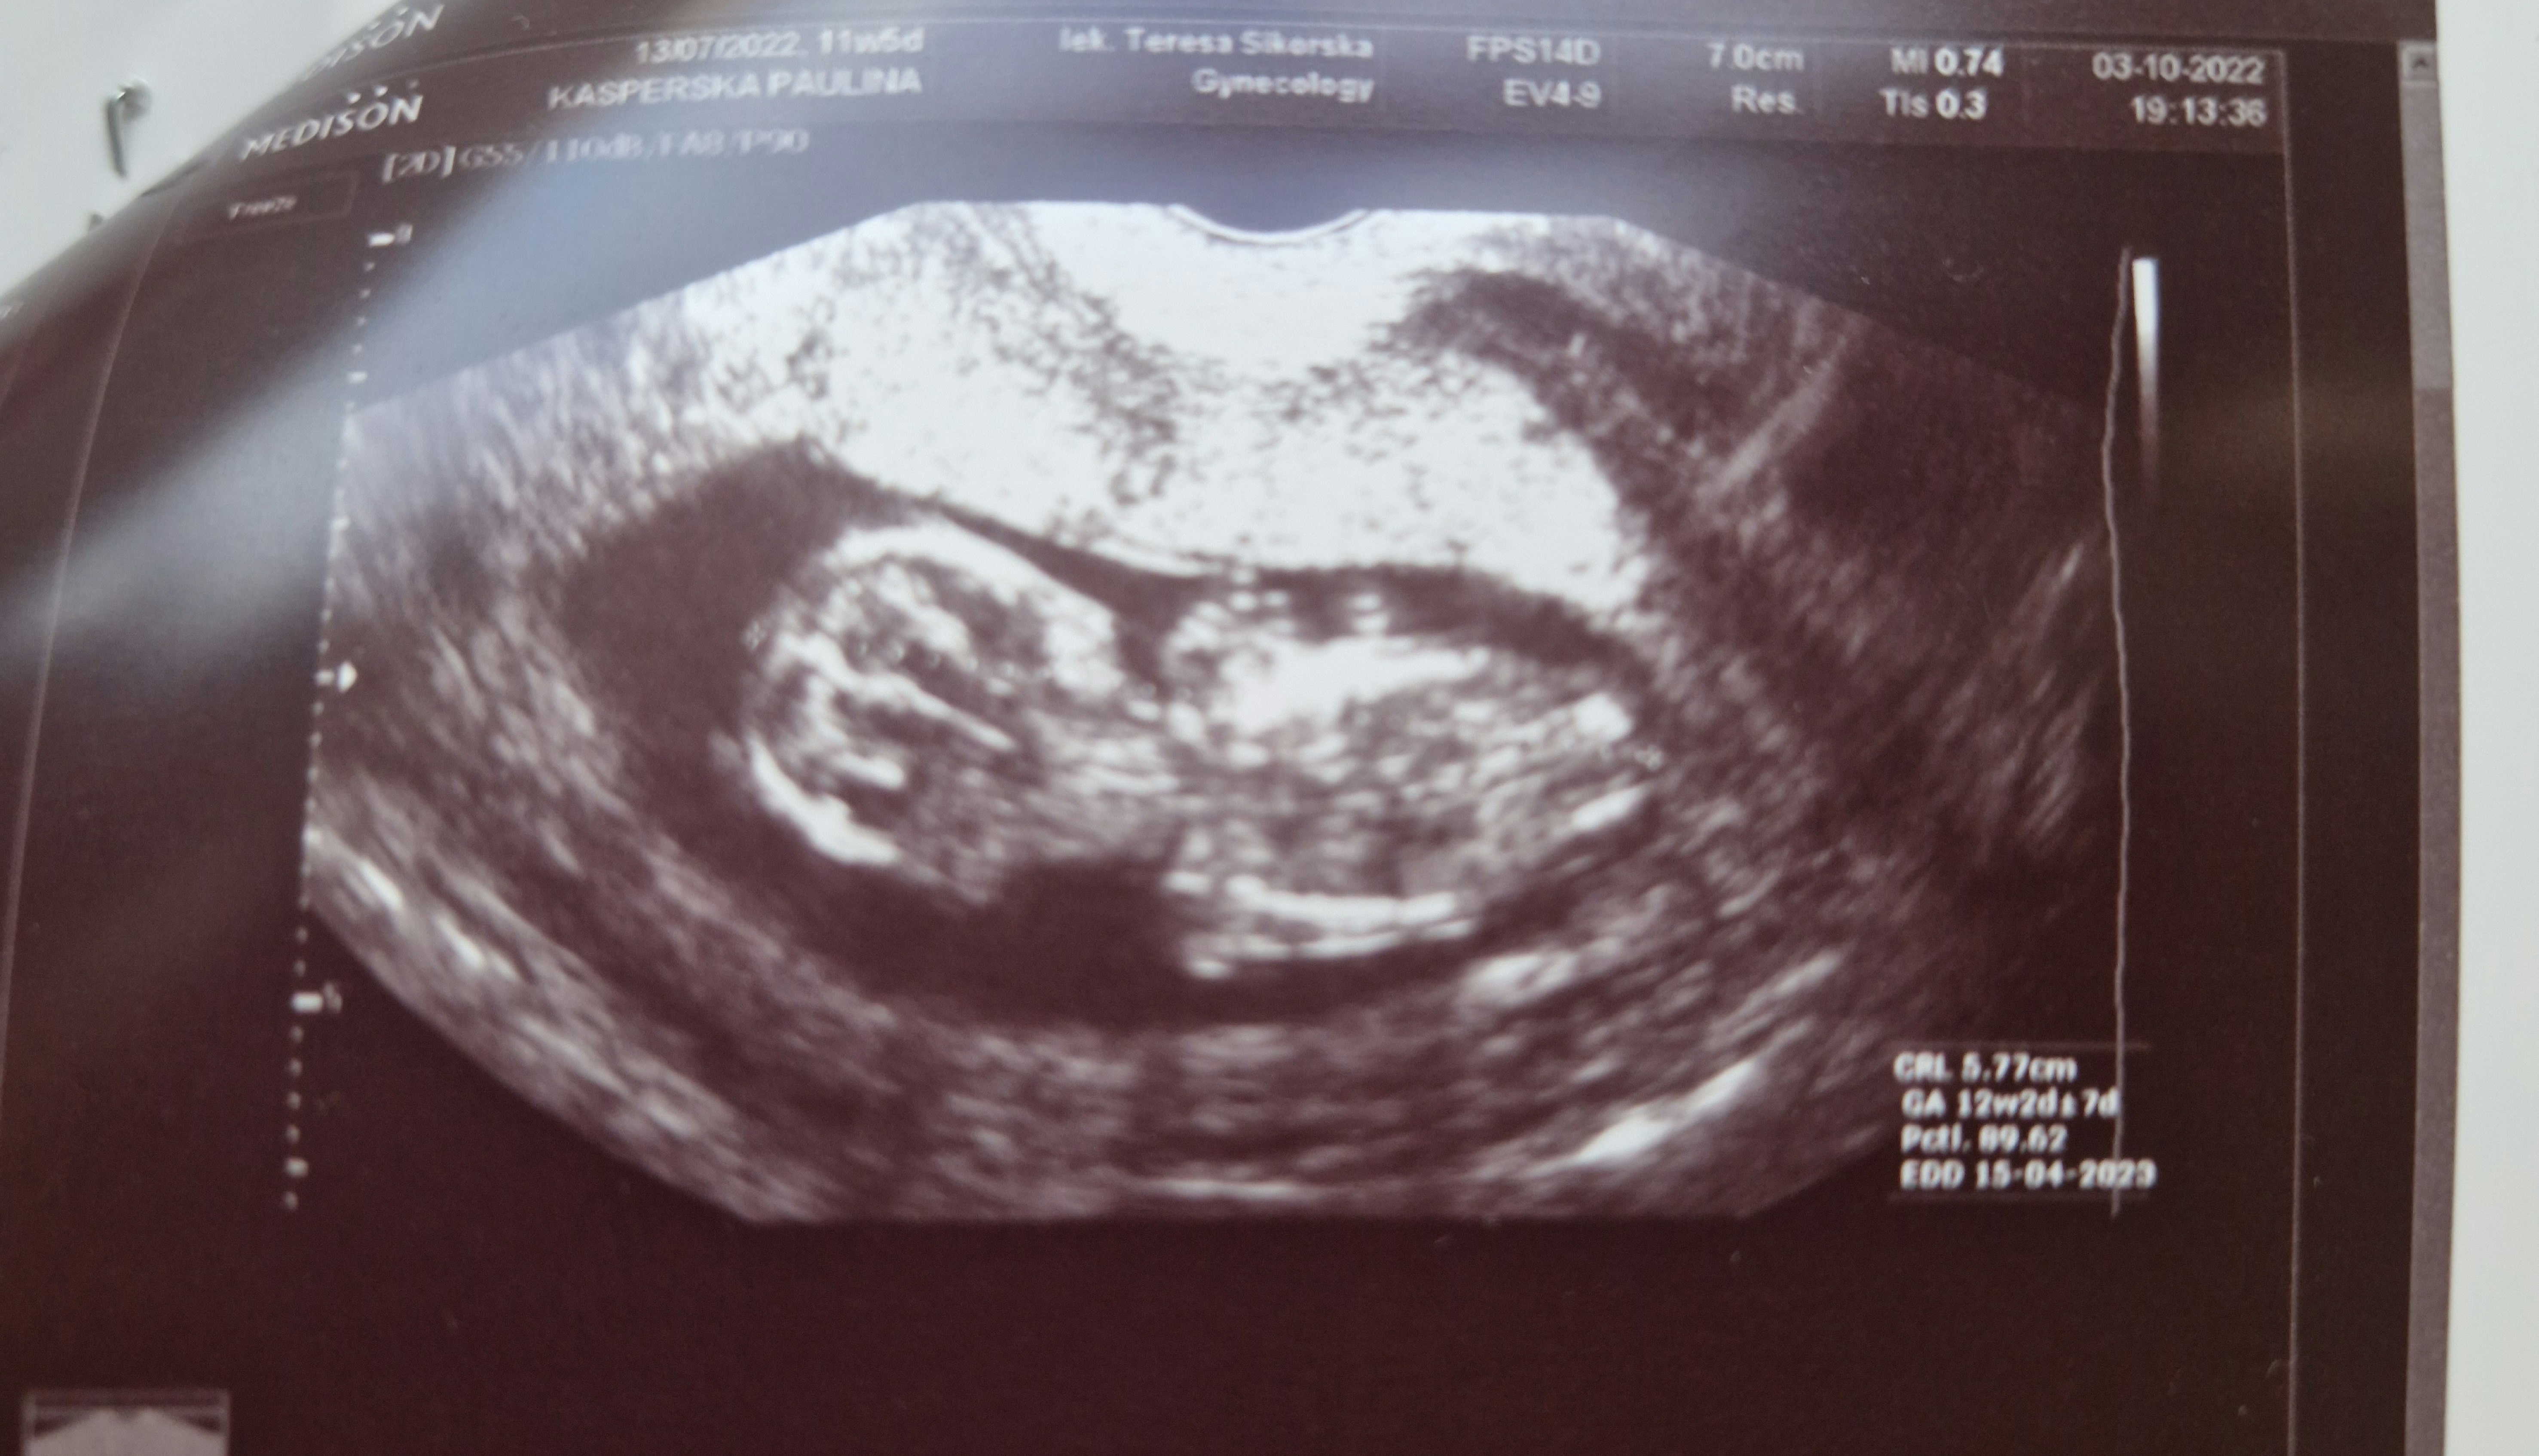

To zaznaczyla mi Pani doktor która stwierdzila ze to chlopiec bo nie możliwe ze kośc ogonowa jest taka długa... w co nie bardzo wierzę bo to 12 tydzień i dziwne zeby byla tak na 100% pewna zwłaszcza ze ona jest juz troche starsza

Mam jeszcze inne zdjecia z tej wizyty moze na nich cos widac (ja sie kompletnie na tym nie znam)